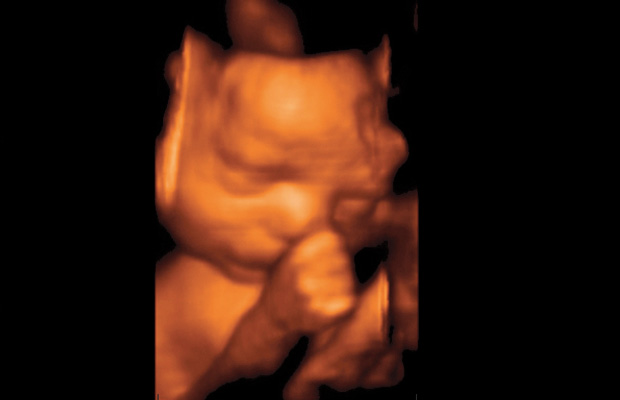

2004 yılında İstanbul’da katıldığım bir Ultrasonografi kongresinde ilk kez 4 boyutlu ultrason ile tanıştım. Bu kongrede anlatılanlardan ve görüntülerden çok etkilendim. Ultrason’u ilk bulan kişinin, gelişmelere bakarak bu konuda daha fazla bir şey yapılamayacağını söylemesi dikkatimi çekti. Ancak o dönemde bilgisayarın olmadığı, aslında 4 boyutlu ve renkli görüntülerin bilgisayar sayesinde oluşturulduğunu öğrendim. Bilindiği gibi Ultrason cihazı sadece ses dalgaları ile çalışan ve hiçbir yan etkisi olmayan bir tanı yöntemidir. 4 boyutlu ultrasonografide de farklı bir dalga boyu gönderilmemekte, 4 boyutlu görüntüyü oluşturan bilgisayar sistemi olmaktadır. Evrende 3 boyut vardır. 3 boyutlu ultrasonda anne karnındaki bebeğin görüntüsü anlık görüntü şeklinde alınır ve 3 boyuttan incelenir. Aynı zamanda bu görüntüden çok ince kesitler alınarak bebeğin iç organları da incelenebilmekte ve anomali (sakatlık) taraması en ince ayrıntılarına kadar yapılabilmektedir.

Evrendeki 4. Boyut ZAMAN boyutudur. Yani ultrasondaki bu 3 boyutlu görüntüyü bebek hareket ederken de alabiliyorsanız o zaman bu görüntü 4 boyutlu olmaktadır. Kısaca anne karnındaki bebeği hem her yönden, hem de hareketli olarak görebiliyorsanız buna 4 boyutlu ultrasongrafik inceleme denir. Bebeğin gerçek görüntüsünü alabiliriz ve doğum sonrasındaki resimlerle bu görüntüler bire bir eşleşmektedir.

Aynı zamanda bebeklerin renkli görüntülerinden bir fotoğraf arşivi düzenledim. Bu fotoğraflardaki ve filmimdeki bebek görüntülerine de birer isim vererek, o anda ne yaptığını biraz da mizahi olarak yorumlayarak ekledim.